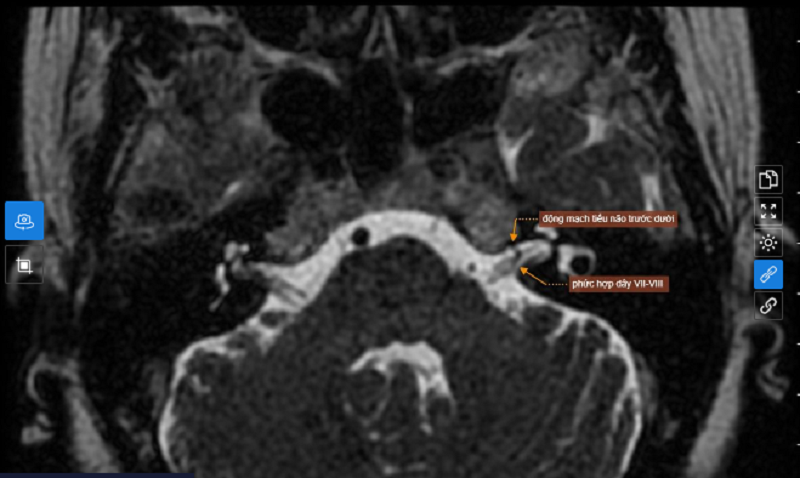

Về chẩn đoán hình ảnh, chụp MRI sọ não có hình ảnh thoái hóa myelin chất trắng dưới vỏ bán cầu đại não và quanh não thất bên hai bên.